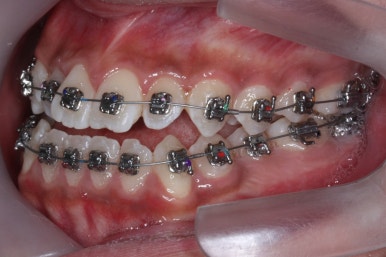

점점 수술전 교정이 진행되는 모습입니다.

각각의 위턱과 아래턱뼈 제위치에 맞게 윗니는 뒤로, 아랫니는 앞으로 내어주게 됩니다. 수술직전까지는 어떻게 보면 교합은 점점 나빠진다고 볼 수 있씁니다.

이 과정에서 힘들어 하시는 분들이 많으신데요. 점점 교합이 서로 멀어질수록 수술은 예쁘게 잘 된답니다.